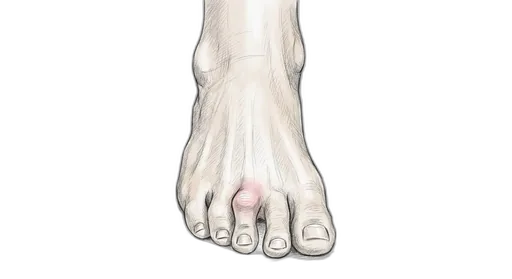

At a glance: A hammertoe is a contracture (permanent bend) of the small joints of the toes, most commonly the second toe. In the flexible stage, you can still straighten the toe by hand — and that's when exercises make the biggest difference. Once the joint becomes rigid, the deformity is fixed and typically needs surgical correction. The exercises here target the intrinsic foot muscles that extend the toes and counterbalance the flexor pull that causes the curling.

Understanding Hammertoe

The small toes work through a tug-of-war between the muscles on top of the foot (extensors) and the muscles underneath (flexors), coordinated by the small intrinsic muscles inside the foot. When the intrinsic muscles weaken — from wearing tight shoes, neurological conditions, or simply from years of disuse — the flexors win and the toes buckle at the proximal interphalangeal (PIP) joint. This creates a raised joint that rubs against the top of the shoe, forming a painful corn. Over time, the tendons and joint capsule tighten, and the flexible deformity becomes rigid. Hammertoes frequently accompany bunions because the big toe drifting sideways crowds the second toe upward.

- One or more toes bent or curled at the middle joint

- A corn or callus on top of the bent joint from shoe friction

- Pain when wearing closed-toe shoes

- Difficulty straightening the affected toe (in rigid stage)

- Pain at the ball of the foot from altered weight distribution